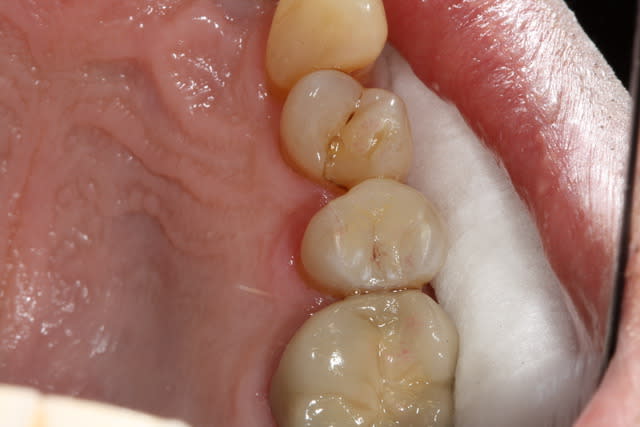

Oune plous pitite ...)))

La 16 est magnifique , le compo de la 4 également (le pan d'émail sert de point de contact , youpi)...

Patient habituel si on peut dire , pris en paro par ma femme , reparti chez un ami...à lui pour les prothèses , reviendu chez moi .

J'ai des bourrages , effectivement c'est ballot et à part refaire les cérams , je ne vois pas .

Pis chuis nul en composite , on va faire un onlay , c'est la seule soluce . Oui je vais en profiter parce que d'ici 2 ans je serai à la retraite , et la moutouelle...là on me rembourse tout . Je vais quand vous faire un devis à tout hasard...)))